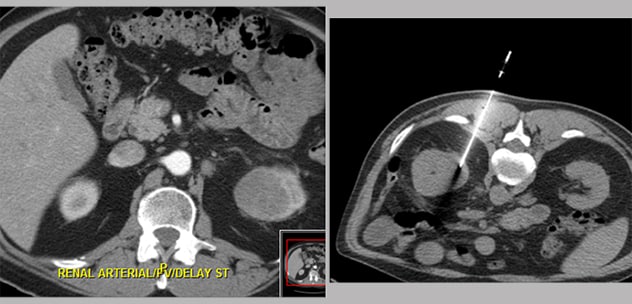

CT-guided percutaneous core needle biopsy of a concerning urothelial lesion.